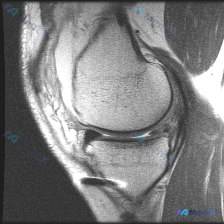

今天遇到一个挺典型的临床情况,整理出来和大家聊聊:核心问题是临床观察提示「软骨异常」,但我们拿到的单幅膝关节MRI冠状位T2加权像分析却全是阴性结果,一起来理理思路。 先给大家放完整影像信息: 1. 整体结构对位:股骨远端胫骨近端对位正常,无骨折错位 2. 骨髓信号:股骨髁、胫骨平台骨髓信号大致均匀...

看到一份膝关节MRI的读片需求,核心问题是半月板异常,我整理了完整的分析思路,分享给大家。 病例影像基础信息 这是一张膝关节矢状位T2加权MRI,观察层面为膝关节外侧室,可显示股骨外侧髁、胫骨外侧平台、外侧半月板体部结构。 系统性影像学发现 1. 骨骼与关节软骨:股骨、胫骨骨皮质信号正常,骨髓无异常...